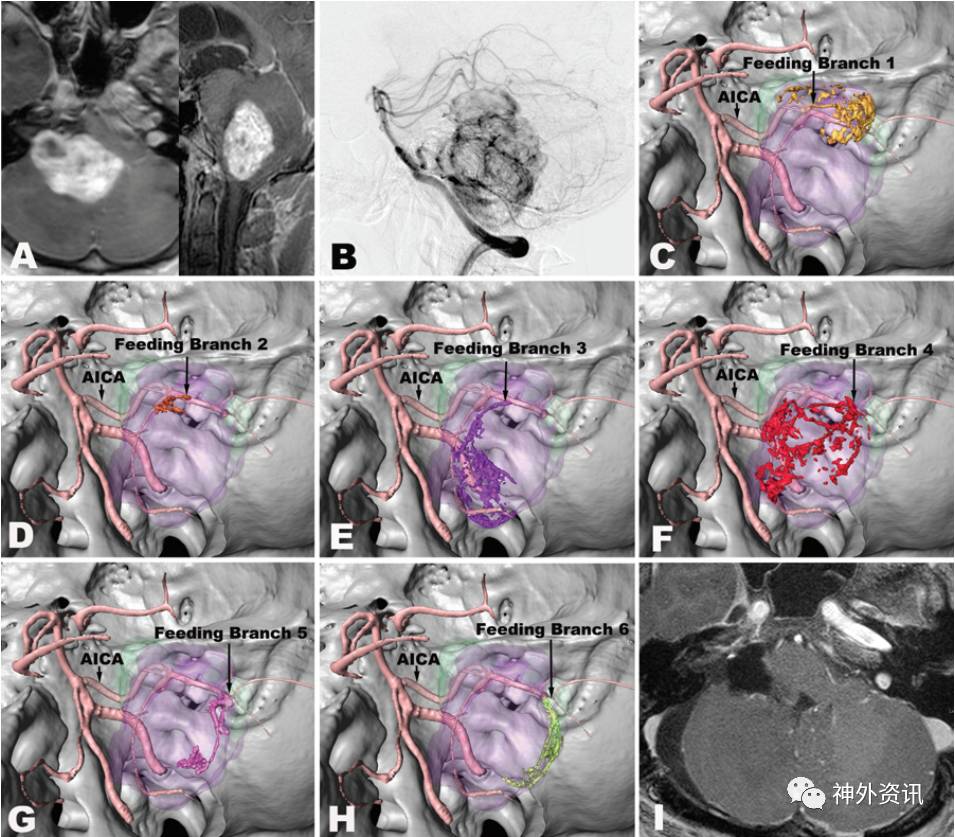

图3. 病例4的影像学资料和hr-3DMMI图像。A.MRI水平位和矢状位T1加权增强成像提示肿瘤位于右小脑半球前外侧部;B.DSA显示肿瘤供血动脉为右小脑前下动脉(AICA);C-H.hr-3DMMI清晰展示肿瘤由右小脑前下动脉发出的6分支供血;I.术后MRI水平位T1加权增强像显示肿瘤完全切除。